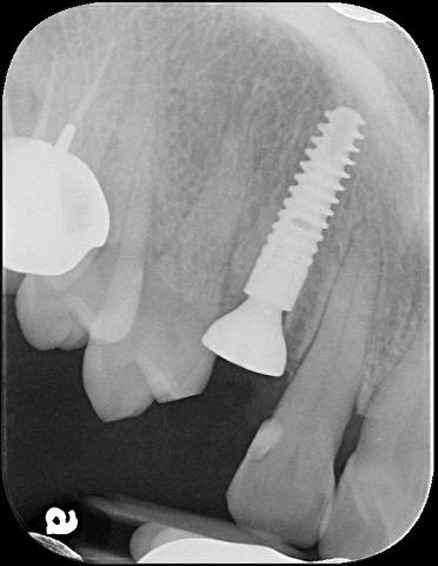

拔牙、立即植牙、補骨

植牙後,角度良好